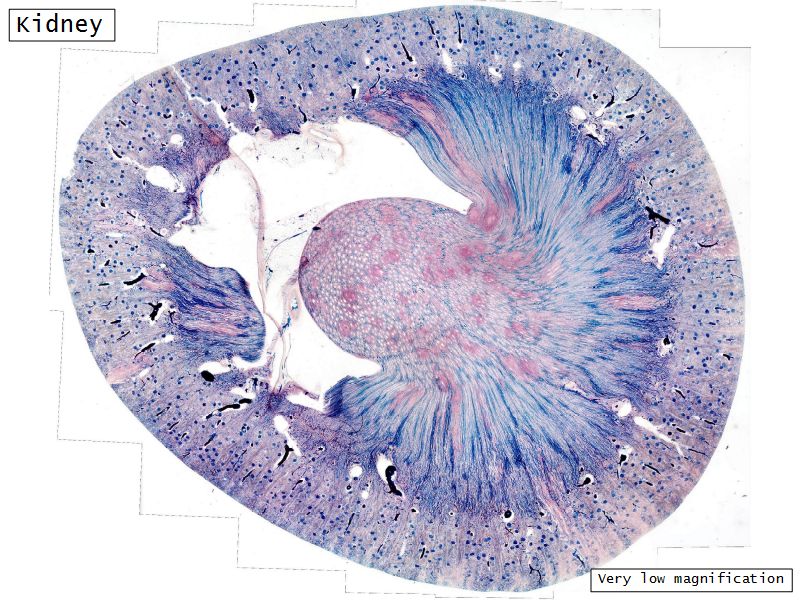

Make an annotated drawing of the macroscopic view of the kidney.

Capsule

Cortex

Medulla

Conical mass (pyramid)

Medullary tissue

Renal columns

Apex of pyramid

Papilla

Projects into renal pelvis

Pyramid

Irregular dense CT

Surrounded adipose tissue